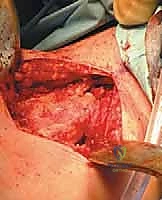

Tumors of the Popliteal Space

A "lazy-S" incision is utilized. The proximal medial limb follows the medial hamstrings (as vessels enter medially from the adductor hiatus), crossing the posterior knee crease obliquely, with the distal lateral limb following the lateral gastrocnemius.

- Neural Identification: Subcutaneous flaps are raised with extreme care to avoid premature penetration of the deep popliteal fascia. The common peroneal nerve is identified first, running deep to the fascia along the medial border of the biceps femoris.

- Deep Exposure: The deep fascia is incised longitudinally. The sciatic nerve is identified centrally. The muscular diamond (hamstrings proximally, gastrocnemius distally) is delineated.

- Vascular Control: The popliteal artery and vein are identified distally between the gastrocnemius heads and proximally at the adductor hiatus. Vessel loops are placed.

- Resection: Exposure can be enhanced by releasing the medial or lateral heads of the gastrocnemius from the femoral condyles. The tumor is resected en bloc.

- Reconstruction: Dead space management is critical in the popliteal fossa. The medial and lateral gastrocnemius heads are tenodesed together over the distal neurovascular structures. The hamstrings are similarly approximated proximally, creating a comprehensive muscular closure over the popliteal space.